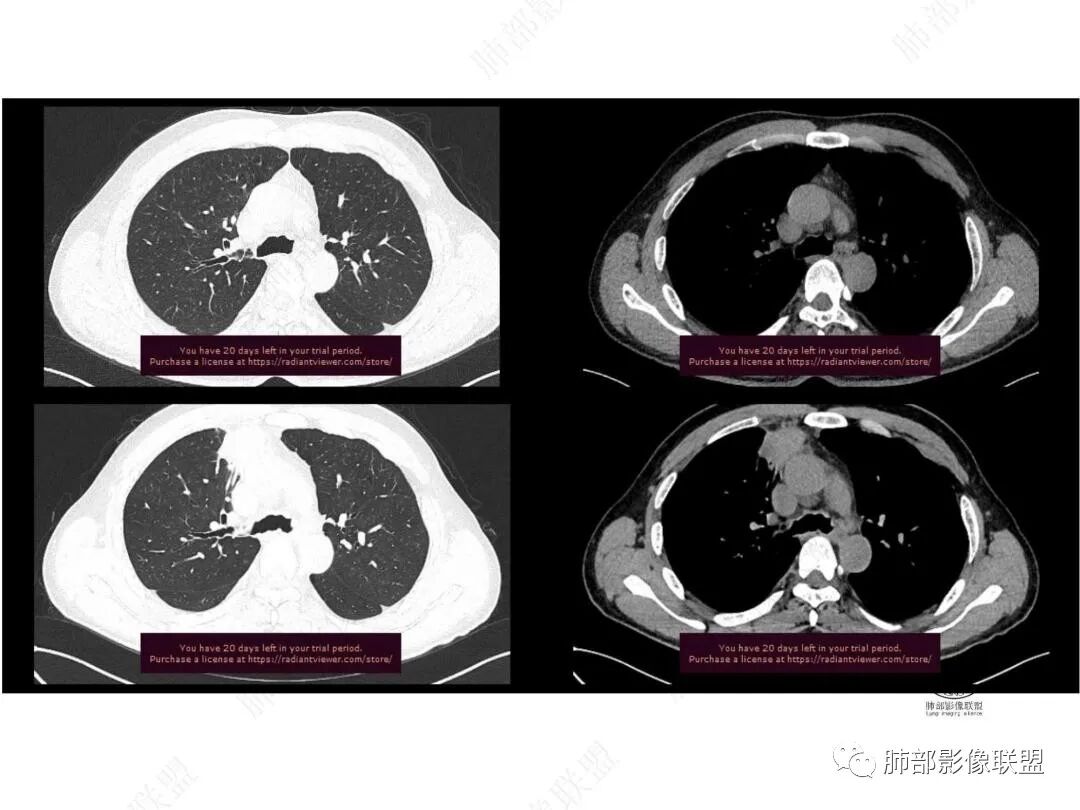

1.中年男性,临床发热,症状较轻,中长病程,炎性指标轻度增高。

2.右肺上叶纵隔旁新发实性密度病灶,密度均匀,轻度强化,未见空洞、液化坏死及钙化,血管穿行自如,支气管进入后狭窄截止。灶周磨玻璃影边界不清,病灶未见明显分叶毛刺,平直、轻度收缩、周围偶见结节影,但未见树芽征。注意纵隔胸膜侵入或突入比较明确。纵隔淋巴结轻度增大。

3.右肺容易想到的病变有慢性炎症、IGg4相关、新生物(炎性肌纤维母细胞瘤、腺癌等)。但病灶侵入纵隔胸膜应当更符合恶性肿瘤。病程进展及强化等影像特点不支持继发性肺结核。

4.肝脏病灶没有假包膜,没有动脉早期强化,没有肝硬化,未见扩张胆管,未见环形强化,也未显示靶征,缺乏肝细胞肝癌、胆管细胞癌、转移癌或肝脓肿特征。

但回顾性分析,如此少血供确实可以符合淋巴瘤,如果密度更均匀一点的话,这是我们有所忽略的地方。

5.淋巴瘤可以解释影像改变,但仅凭影像及临床很难想到它是霍奇金!结外病变主攻方向以肝组织、肺组织为主,还突破胸膜?

原发性肺淋巴瘤(PPL)是指肺实质或支气管的淋巴组织异常增生,侵犯的主要对象就是肺间质和支气管粘膜下组织,无纵膈、肺门及其他部位的淋巴瘤,在发病时或者确诊后3个月内没有肺外病变的证据,是结外肺淋巴瘤的一种罕见类型,以肺的非霍奇金淋巴瘤(NHL)多见,其中NHL肿最常见的就是结外边缘区黏膜相关淋巴瘤组织(MALT)淋巴瘤,其次是弥漫大B细胞淋巴瘤。肺MALT淋巴瘤是较为罕见的低度恶性肿瘤,多见于50-70岁,男女发病率无明显差异,或男性略多于女性

国外多名学者的影像-病理研究报道认为其病理学基础是由于肿瘤细胞沿支气管血管束周围间质及胸膜浸润生长,形成小叶间隔增厚、支气管血管束增粗等间质性改变,进一步浸润肺泡壁、充填肺泡腔。

病灶可表现为:表现为实变、结节及磨玻璃影。

①实变的出现率100%,多表现为两(89%)或单肺多发,密度均匀,与邻近胸壁肌肉的密度大致相等,少见钙化(15%),这与病灶内血管保持 完整,血供丰富,且肿瘤生长缓慢,对缺氧耐受好,不易坏死有关。边缘磨玻璃影或晕征具有特异性,其病理学基础是肿瘤细胞对小叶间隔、肺泡壁的淋巴瘤样浸润;

②其余肺叶磨玻璃影或结节常见(67%), 多沿支气管血管束分布;可表现为病灶周围间质性改变,磨玻璃密度影或晕征及树芽征象,周围组织间质增厚并且有结节感,病理基础为肿瘤细胞浸润细支气管周围间质及肺泡壁。

其中实变是其特点,胸膜下或支气管血管束节段性分布具有特征性,跨叶征较常见。

病灶的密度:密度均匀,部分病灶内可见空洞及气液平,轻中度均匀强化。

病灶的边缘:有膨隆,浅分叶,也有平直、收缩,平直收缩是因为肿瘤组织浸润致肺泡塌陷及周围纤维组织增生,牵拉正常的肺组织向病灶中心形成聚拢状改变,似呈“炎性”改变。

支气管充气征伴或不伴支气管扩张:

肿瘤细胞沿肺间质及支气管黏膜下组织浸润,支气管管壁未见明显破坏,管腔内未见肿瘤细胞充填,呈现充气支气管征;充气支气管走行自然,无扭曲、僵硬,内壁管腔光滑,支气管管壁见增厚并常有管腔的扩张,含气支气管可呈串珠样不均匀扩张,扩张明显处呈空腔样或皂泡样的囊状含气影;

血管造影征:

肿瘤组织浸润引起间质增厚、肺泡壁破坏、肺泡腔充填,而周围充盈血管走行自然,未受肿瘤侵犯。